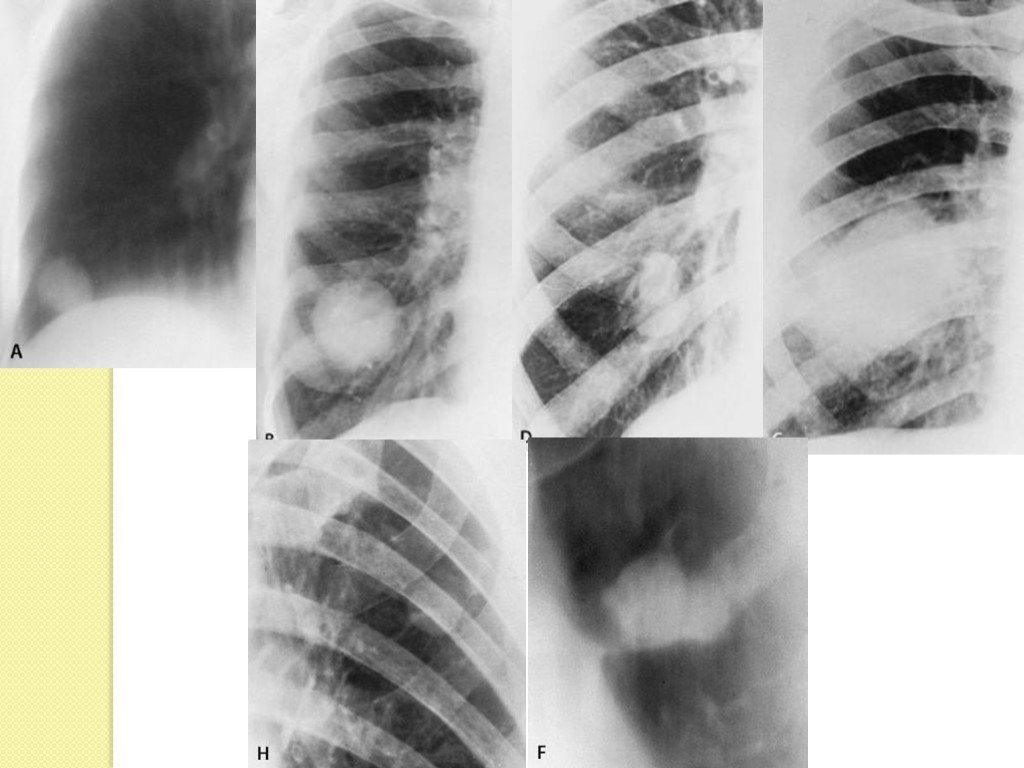

Медицинские аспекты заболеваний: рентгенологическая картина туберкулеза костей

Раздел: Снимки-откровения